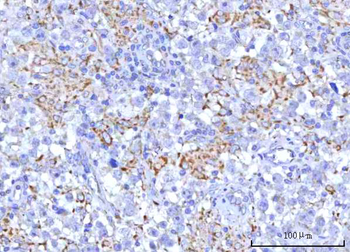

IHC staining of FFPE human lymph node with CD72 antibody (clone BU40). HIER: boil tissue sections in pH9 10mM Tris with 1mM EDTA for 20 min and allow to cool before testing.

IHC staining of FFPE human lymph node with CD72 antibody (clone BU40). HIER: boil tissue sections in pH9 10mM Tris with 1mM EDTA for 20 min and allow to cool before testing.